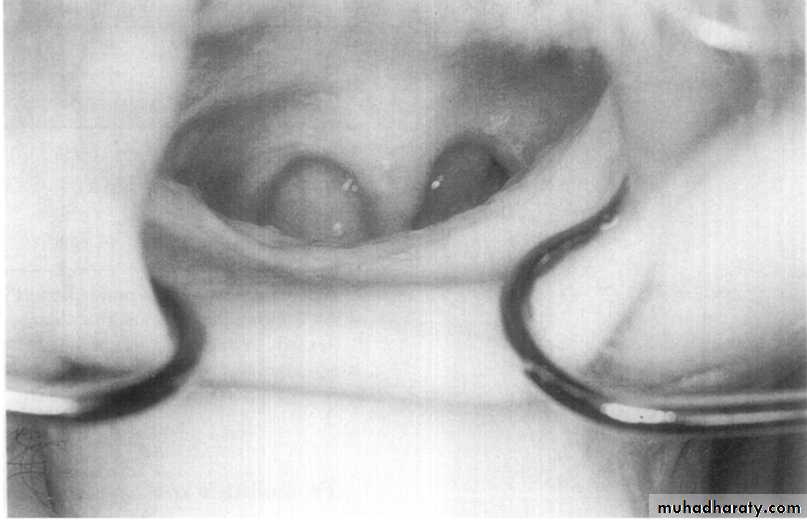

Source: Hoekema A, Stegenga B & de Bont M. 2010.Tongue retaining appliances

(TRA)

Action by:

• reposition the tongue in an anterior position by securing it with negative pressure in a soft plastic bulb.• with plastic depressor that comes into direct contact with the tongue base.

Limitation:

• Compromising nasal passage.

• Discomfort and loss of negative pressure in the bulb.

• Made from non rigid vinyl material & the patient is instructed to protrude the tongue into the hollow bulb & the vacuum hold it there for at least 6 hours of sleep.

Disadvantage: can cause tongue tip soreness, due to the suction; that lead to difficult accommodation of the appliance.

Advantage: The Tongue advancers, since they’re not stretch the mandible, so the TMJ symptoms would not be exceeded from the usual.